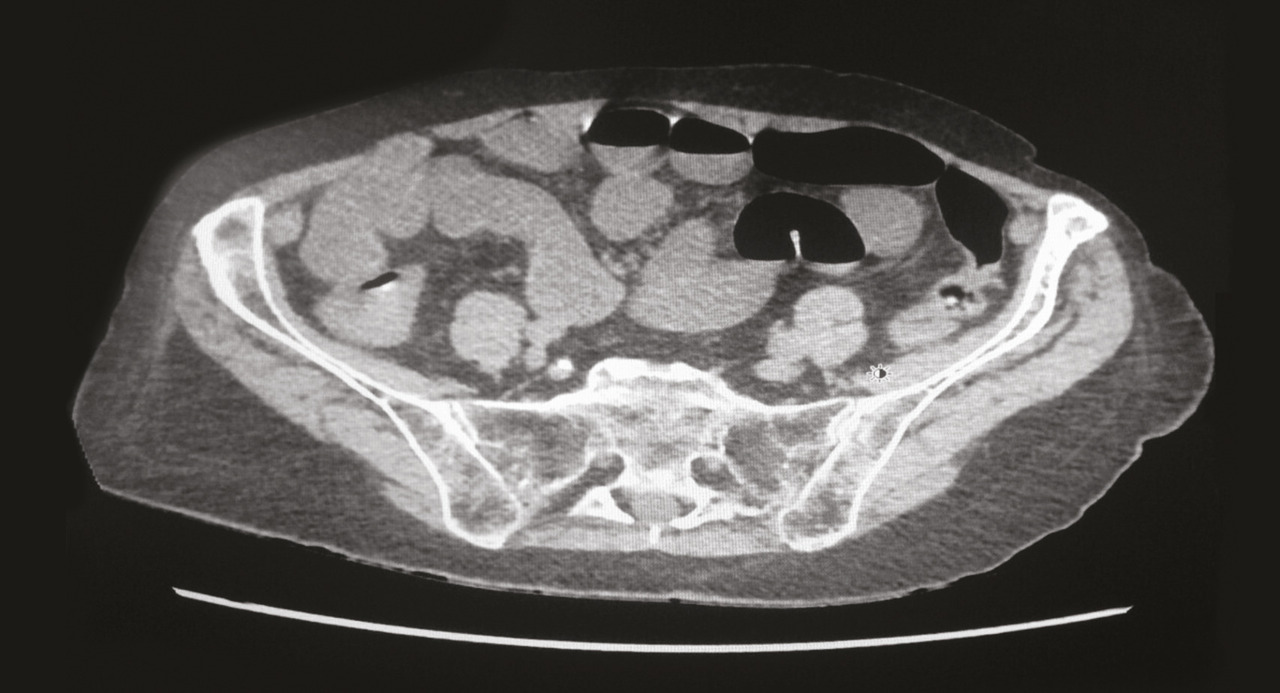

Devant ce tableau fortement évocateur d’un syndrome occlusif, le scanner abdominopelvien injecté par produit de contraste iodé met en évidence un syndrome occlusif grêlique sur un iléus réflexe dû à une appendicite aiguë incarcérée dans une hernie inguinale droite directe, avec distension et stase liquidienne de toutes les anses grêles en amont et de l’estomac, sans signe de souffrance pariétale digestive (fig. 1 et 2).